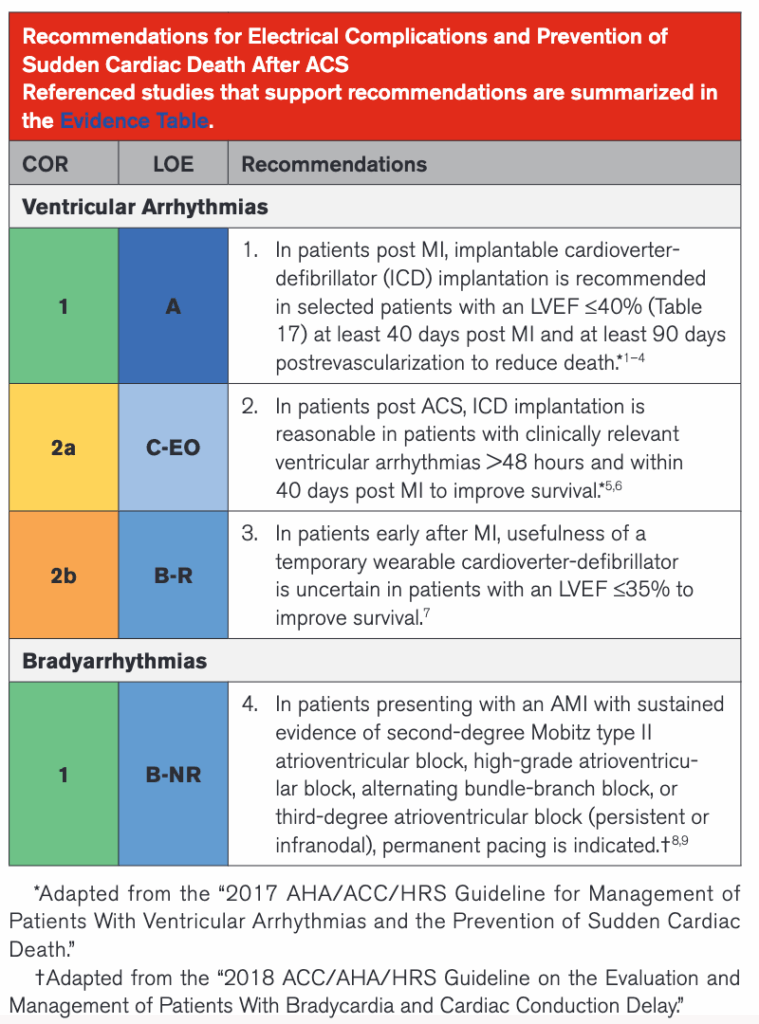

La frecuencia sigue subiendo hasta instaurarse una Taquicardia Ventricular (TV) monomórfica con pulso con 170 lpm y sin cambios clínicos en la paciente (conciente pero aletargada, tiempo de llenado capilar largo y presión arterial 106/68 mmHg).

Y, ahora, ¿qué hacemos? Pues dar manejo a la taquiarritmia inestable (ventanas clínicas de hipoperfusión tisular positivas en esta mujer). Veamos puntos clave recomendados en el Algoritmo de Taquicardia con Pulso2 del manual ACLS vigente al día de hoy:

En nuestra paciente la taquiarritmia generó alteración del estado mental y tiempo de llenado capilar distal, por lo cual realizar una cardioversión sincronizada estaba indicado. ¿Qué pasó después? Eso lo dejaremos para otra ocasión.